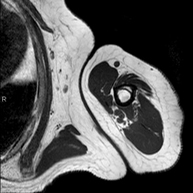

Prueba diagnóstica no invasiva que consiste en la obtención de imágenes de alta definición anatómica de la región escrotal mediante el empleo de un campo electromagnético y ondas de radio (con un emisor y un receptor). No utiliza radiación ionizante. En ocasiones se deberá emplear contraste paramagnético (Gadolinio) para completar el estudio. Se utiliza para el estudio detallado de los testículos, para identificar posibles tumores u otras patologías, además de poder visualizar alteraciones de las estructuras adyacentes. - RM Peneana